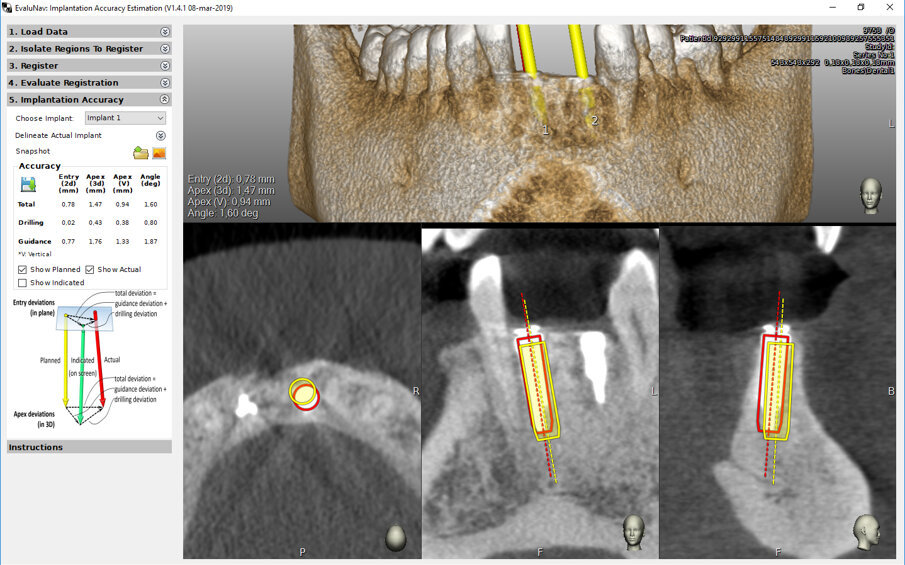

La prima e più importante difficoltà ad approcciare questo tipo di chirurgia è l’ergonomia e l’organizzazione del campo chirurgico. Si deve fare in modo che nulla possa toccare o dislocare i reperi, soprattutto quelli presenti sul paziente, il che corrisponde a starare il sistema. Nel protocollo Trace&Place questo non corrisponde ad un grosso problema dal momento che, nel corso della procedura, è possibile riprendere la tracciatura e ritornare ad una accuratezza clinicamente accettabili ma ruba comunque tempi all’intervento. Gli interventi sulle emiarcate sinistre, specie quella inferiore, può richiedere di lavorare con la mano sinistra; ho trovato molto utile in questi casi la posizione ad ore 3. L’uso della mano sinistra non deve spaventare dal momento che questo tipo di chirurgia richiede di impugnare gli strumenti a due mani con un dito che stabilizzi la punta nella direzione ricercata. La seconda difficoltà è la necessità di lavorare con un approccio di chirurgia robotica, con gli occhi non puntati sul campo chirurgico ma su uno schermo: psicologicamente può essere un muro importante da superare ma solo fino ad aver acquisito la sufficiente fiducia nel sistema e, soprattutto, nella fase di verifica della accuratezza. Il Navident® by Claronav® infine viene fornito completo di un software, Evalunav ®, attraverso il quale è possibile verificare l’accuratezza della nostre procedure chirurgiche sfruttando una TAC post-posizionamento (Fig. 15). Tutto questo al servizio di una chirurgia flapless od open secondo le esigenze o necessità (Fig. 16).

Fig. 15 - Il software Evlunav® by Claronav® per la valutazione dell’accuratezza del posizionamento implantare rispetto alla pianificazione.